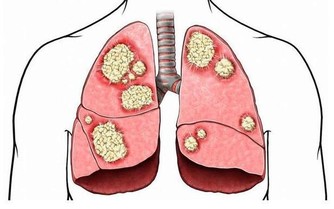

有癌症家族史,是不是一定逃不過癌症?

實際上,目前我們已經發現了數百種癌症,每個都具有獨特的分子特徵和可變的臨床表達。比如,在神經腫瘤學中,已經確定了至少120種腦和脊髓癌亞型。對於這種多樣化的敵人,我們的診斷和治療方法必須擴大,也必然很難。

4. 擁有“癌症基因”意味著你注定要患癌症

即使你的直系親屬中有人患過癌症,即使你身上已經出現基因突變,也不是無法避開癌症的。我們的新陳代謝和細胞中有許多錯綜複雜的途徑,其中一些途徑可以打開基因,有些可以將它們關閉。這是一個叫做“表觀遺傳學”的領域,環境和外部影響可以改變基因表達。於是,這使得患者有能力做一些事情,比如吃健康的飲食和鍛煉,這可能會影響最終結果。